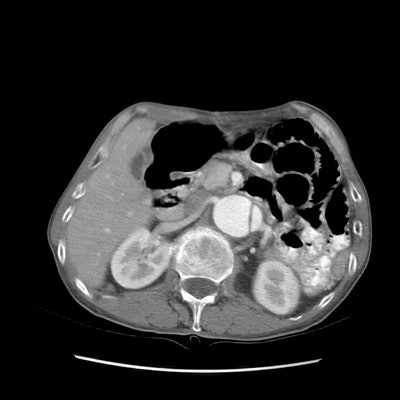

Type B dissection on CT:

The images below demonstrate a Type B aortic dissection beginning at the level of the thoracic outlet (note also aortic aneurysm). Both the superior mesenteric artery and the left renal artery arise from the false lumen. (Click images to enlarge)